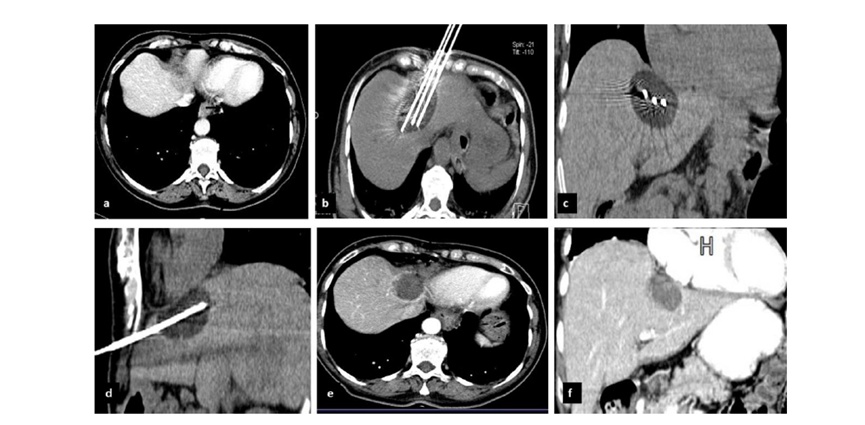

79 歲男性,肝轉(zhuǎn)移(結(jié)直腸癌)腫瘤的完全消融病例

( a ) 軸向 MRI 和 ( b ) 軸向 CT 顯示肝S8段有一個(gè)16mm的病灶,鄰近肝緣。( c )冷凍消融期間CT顯示放置了2個(gè)冷凍探針,低密度冰球包圍病灶。(d)術(shù)后1個(gè)月隨訪 CT顯示冰球?qū)?yīng)的壞死區(qū)域,未見復(fù)發(fā)。(e)術(shù)后6個(gè)月的CT,壞死區(qū)域縮小,未見復(fù)發(fā)。(f)與基線影像(g)相比,12個(gè)月后的FDG-PET/CT顯示未見FDG攝取。

62歲女性,肝轉(zhuǎn)移(卵巢癌)腫瘤的完全消融病例(a)軸向CT顯示病變位置毗鄰心臟和上腔靜脈(黑色箭頭)。(b)術(shù)中軸向CT掃描:使用三個(gè)冷凍探針。1個(gè)月后的軸向(e)和冠狀位(f)增強(qiáng)CT掃描顯示低密度區(qū)域,由于肉芽組織反應(yīng)引起的邊緣增強(qiáng)。

技術(shù)成功100%,92% 的病灶中觀察到腫瘤完全消融。16 名患者 (33%) 出現(xiàn)局部復(fù)發(fā)。10 名患者 (20%) 因局部復(fù)發(fā)或腫瘤消融不完全而接受二次冷凍消融術(shù)。

7名患者出現(xiàn)輕微并發(fā)癥,未發(fā)現(xiàn)膿腫形成、膽漏、膽汁瘤或血液學(xué)變化。冷凍消融可安全、有效治療毗鄰重要臟器的原發(fā)性肝臟腫瘤和肝轉(zhuǎn)移瘤患者,有效控制腫瘤局部進(jìn)展,使患者生存獲益。我國作為肝癌大國,對于肝癌的治療一直給予高度重視?;趯<夜沧R和相關(guān)文獻(xiàn)研究結(jié)果顯示,冷凍消融技術(shù)具有高效、低成本、創(chuàng)傷小、適應(yīng)證廣、并發(fā)癥相對較少等優(yōu)點(diǎn),可有效延長患者生存期、提高生活質(zhì)量、降低患者經(jīng)濟(jì)負(fù)擔(dān)。因此,冷凍消融技術(shù)在肝癌的應(yīng)用中有著極高的潛力和廣泛的發(fā)展空間。